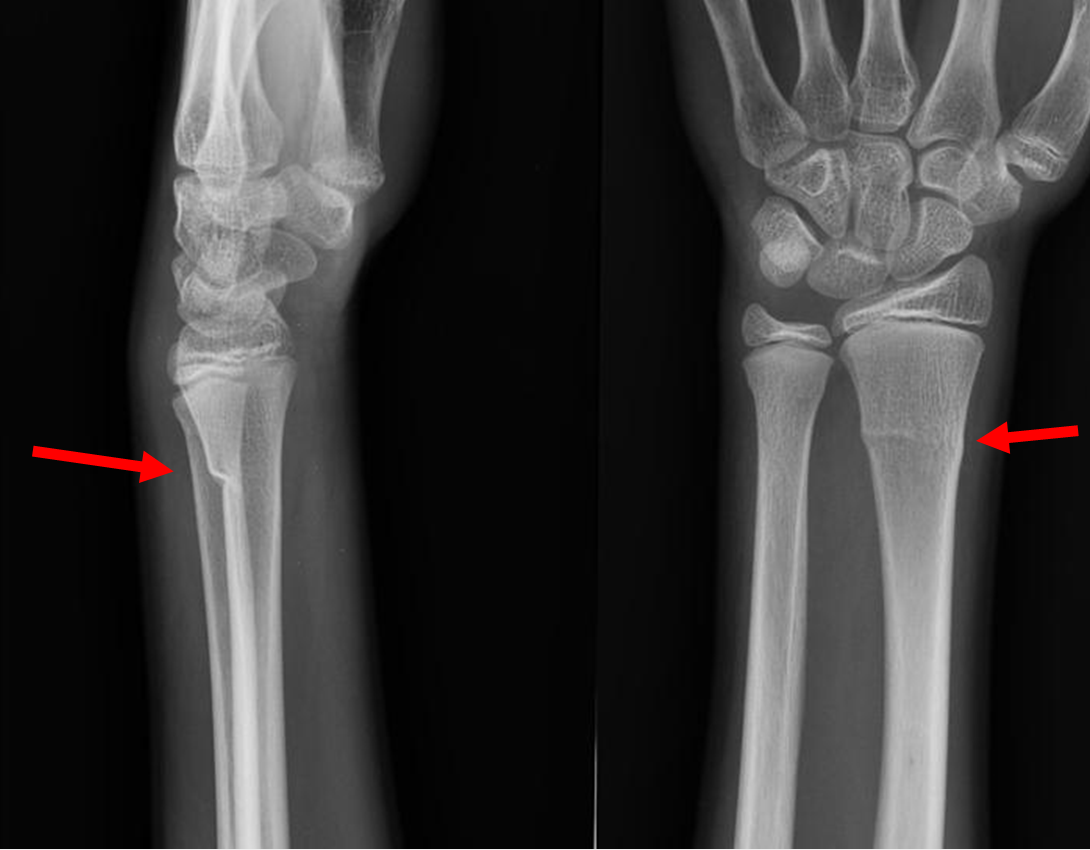

Example xray of greenstick fracture of distal radius:

(demonstrating extension of fracture line to volar cortex with angulation of the volar cortex)

Images from:

Royal Children's Hospital Melbourne - Greenstick fracture distal radius